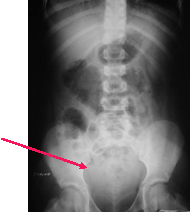

There is a soft tissue density above the urinary bladder in the

pelvis. This is the appearance of free fluid in the peritoneal cavity, a

consequence here of a ruptured spleen.